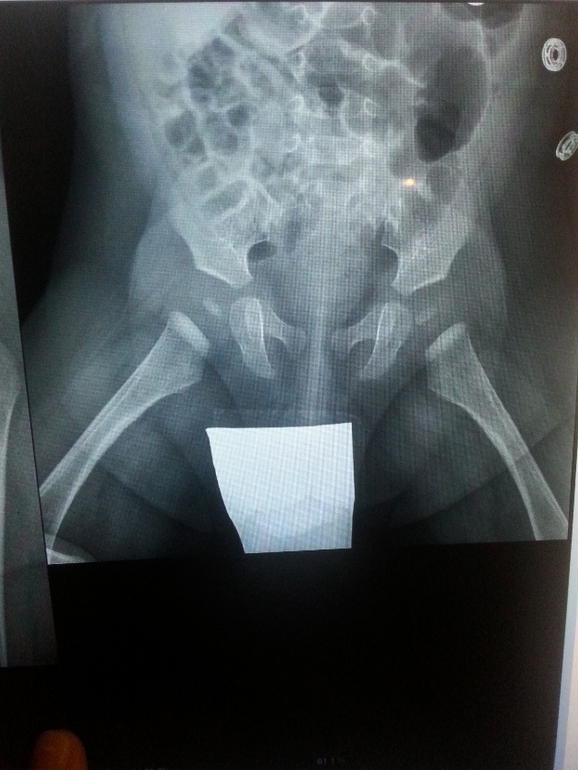

Добрый вечер! прошу подскажите нам в нашей ситуации. В 3месяца сына делали УЗИ тбс планово в нашей поликлинике.В заключении написано: тазобедренные суставы без особенностей, без эхоструктурных изменений. ядра еще не окостенели. в 4месяца только нас направили к ортопеду так же планово (поздно,вот такая у нас поликлиника.к слову старшего сына к ортопеду не направляли ни разу, только к хирургу). ортопед один раз развел сыну ноги, сказал "что-то не нравятся мне ваши ноги" и направил на УЗИ тбс. Мы пошли сделали УЗИ в этой же поликлинике. узистка ничего не сказала, пока я ей не указала на то,что нас направил ортопед с подозрением на дисплазию. тогда она стала смотреть внимательнее и говорит"а, да,есть".намеряла нам углы (на всякий случай для ортопеда,если он спросит): правый тбс альфа-65 и бета-56, левый тбс альфа-57 и бета-83(!!!). Мы в данном УЗИ засомневались и пошли в платный центр. по отзывам там работает очень хороший узист.вот его заключение:правый сустав- положение головки центральное, контур головки ровный, визуализируется ядро окостенения. хрящевой угол альфа-60, бета-44.левый сустав- положение головки центральное, контур головки ровный, визуализируется ядро окостенения. хрящевой угол альфа-63, бета-44.Эхо-признаки на момент осмотра патологии не выявлено.В 4.5 мес мы так же сделали рентген в 2-х проекциях. заключение-головки бедренных костей центрированы, находятся в суставах. вертлужные впадины незначительно скошены.ацетабулярный угол равен 22 градуса с обеих сторон. рентгенолог сказал,что признаков дисплазии не видит. Пошли с результатами УЗИ и снимком рентгена к ортопеду. данные УЗИ он даже смотреть не стал (хотя изначально направлял нас именно на УЗИ). покрутил снимок и сказал сначала,что ничего такого, а потом что ему все равно,что там намерил рентгенолог(рентген цифровой), он и так видит без измерения,что оба угла больше 25 градусов.(???). и назначил нам подушку Фрейка на 3месяца, добавив,что ее купите в аптеке такой-то,потому что именно там подушки продаются помягче(???). ну еще можем поделать массаж и ЛФК. Я в недоумении. Отправляла снимок рентгена на почту доктору Колесову В.В.,он ответил,что патологии тбс у ребенка нет и лечения не требуется. Я в недоумении. Что делать? Других ортопедов в нашем городе вроде бы нет,я узнавала,только хирурги. Я отсылала снимки онлайн еще нескольким ортопедам,пока тишина. Может,кто знающий посмотрит на снимки. Подушку Фрейка одевать мы не стали,муж категорически против,тем более что стоит вопрос о том,нужна ли она вообще. Может,действительно нет никакой дисплазии.![]()